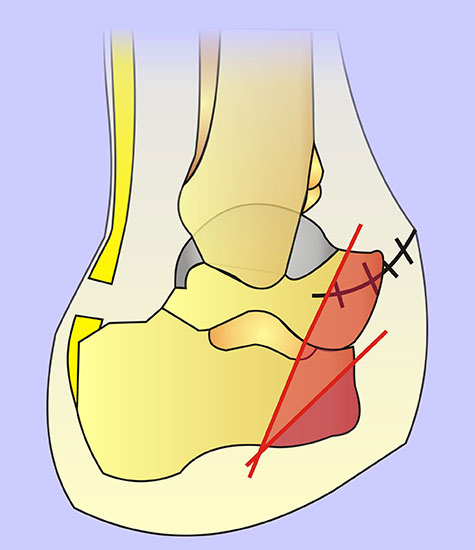

Schema der Amputationsniveaus am Fuß von der Seite.

Grün: empfohlene Amputationslinien.

Rot: nicht empfohlene Amputationslinie.

Abbildung 1

Die Amputationslinien am Fuß, die sich uns bewährt haben, sind in der Abb. 1 schematisch dargestellt.